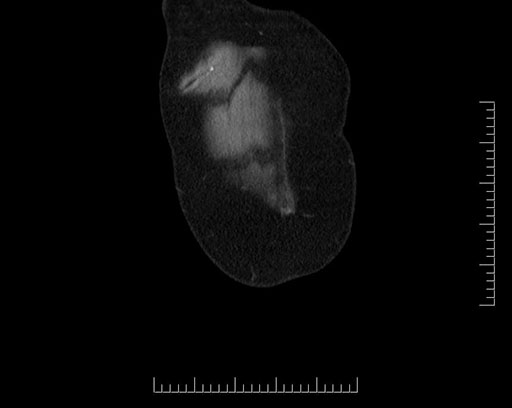

Axial - 3 months prior